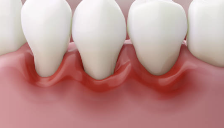

✅ 2. 잇몸이 붓고 붉은빛을 띤다

건강한 잇몸은 연한 분홍빛인데,

치은염이 있으면 잇몸이 붉게 변하고 부풀어 오른 느낌을 줍니다.

특히 치아 경계 부분이 뚜렷하게 부어 보이거나

미세한 통증·불편함을 동반할 수 있어요.